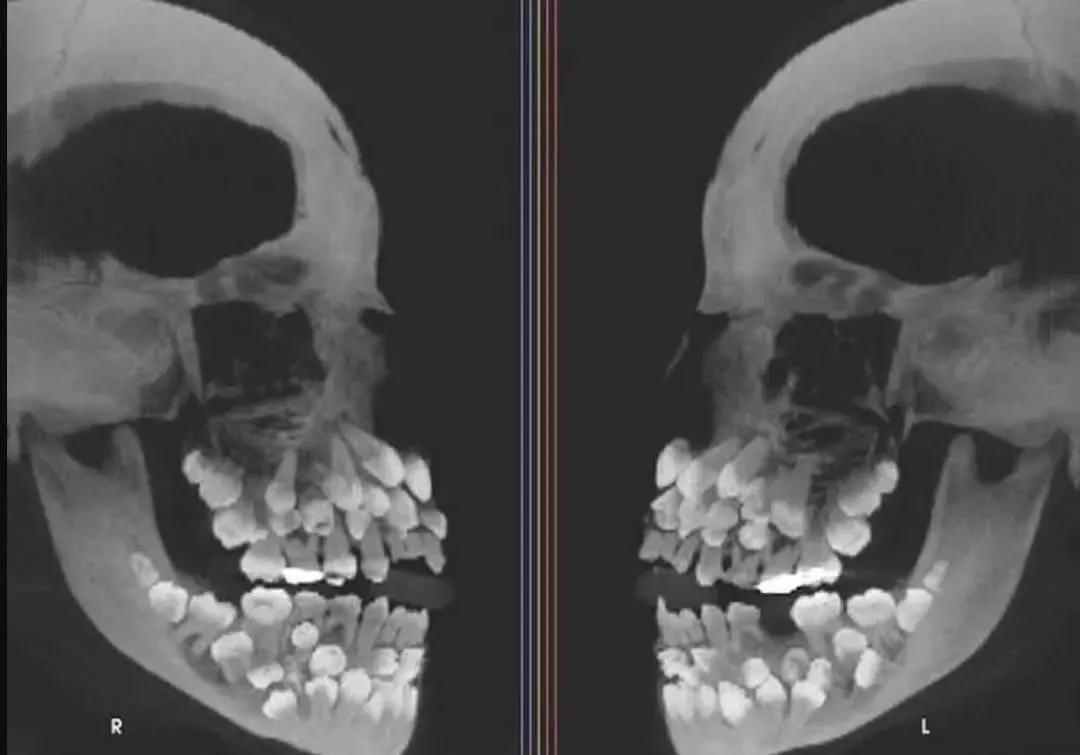

ในช่วงกลางปี 2025 โลกออนไลน์ต่างพากันแชร์ภาพเอกซเรย์สุดแปลกประหลาดอีกครั้ง ภาพของเด็กหญิงวัย 11 ปีจากประเทศบราซิล ที่มีฟันรวมมากถึง 81 ซี่ — มากกว่ามนุษย์ปกติถึงกว่า 2 เท่า จนกลายเป็นหนึ่งในเคสภาวะฟันเกิน (Hyperdontia) ที่หายากและน่าทึ่งที่สุดเท่าที่เคยถูกบันทึกไว้ในวงการทันตแพทย์

แม้ภาพนี้จะถูกเผยแพร่ครั้งแรกในปี 2013 แต่ทุกครั้งที่มันกลับมาโผล่บนโซเชียล ก็ยังสร้างความตกตะลึงไม่แพ้กัน ทั้งจำนวนฟันที่มากผิดปกติ โครงสร้างที่ซ้อนกันแน่นภายในขากรรไกร และรายละเอียดทางการแพทย์ที่นักททันตกรรมเองยังยืนยันว่าเป็น “หนึ่งในกรณีศึกษาที่ท้าทายที่สุด”

ในภาพเอกซเรย์จะเห็นว่าเด็กหญิงคนนี้มีฟันดังนี้:

ฟันน้ำนม 18 ซี่

ฟันแท้ 32 ซี่

ฟันเกิน (Supernumerary teeth) 31 ซี่

รวมทั้งสิ้น 81 ซี่ในช่องปากเดียว

จำนวนนี้มากกว่ามาตรฐานมนุษย์ซึ่งทั่วไปมีฟันแท้เพียง 32 ซี่ เท่านั้น

นั่นหมายความว่า ฟันของเธอมากกว่าคนอื่นถึง 2.5 เท่า!

ทำให้ภายในขากรรไกรปรากฏฟันเรียงกันแน่นทับซ้อนกันหลายชั้น จนเป็นที่มาของภาพที่ทั้งแปลกประหลาดและน่าทึ่งในเวลาเดียวกัน